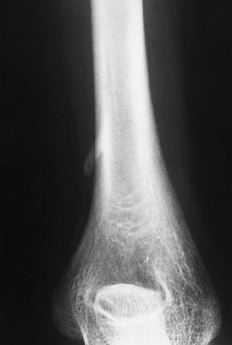

Mediante un acceso medial se alcanzó a la zona por el lado posteromedial del músculo bíceps. Se pudo observar la presencia de una prominencia ósea con un refuerzo fibroso que se dirigía desde la punta de la misma hacia la epitróclea, correspondiendo al denominado ligamento de Struthers (Fig. 2); algunas fibras musculares del pronador redondo se insertaban en la zona más distal de la apófisis. Tras la exposición de la apófisis se apreció su forma de gancho, con una base amplia y de unos 2 cm de longitud, situada en la cara anteromedial del húmero, que se dirigía hacia abajo, adelante y medialmente. En contacto con su cara interna (cubital) se distinguía el nervio mediano y, más medialmente, la arteria humeral, sin que ninguna de estas estructuras presentara alteraciones. No se evidenció ninguna estructura neurovascular en la zona lateral (radial) de la apófisis. Tras la disección anatómica, nerviosa y vascular se procedió a la resección de la exóstosis mediante escoplo, tallando un cajeado de la base de implantación en el húmero (Fig. 3). El período postoperatorio transcurrió sin alteraciones y a los 12 días se retiró el vendaje y los puntos. En la revisión a los 6 meses la paciente estaba asintomática y sin evidenciar signos de recidiva en la radiografía.

Figura 2. Imagen previa a la resección de la apófisis donde se observa el ligamento de Struthers (flecha).